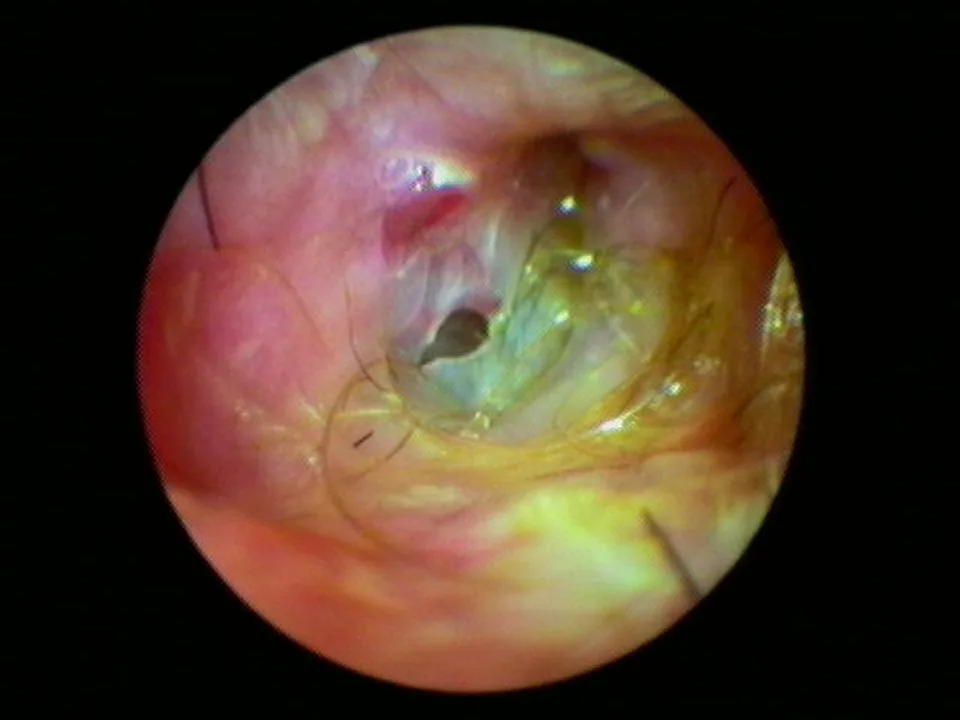

Visualization of fluids (eg, blood, pus, mucus, serum) behind the eardrum in the middle ear (Figure 2)

FIGURE 2 Left middle ear inflamed with exudate and blood behind eardrum (left). The normal right eardrum is shown for comparison (right).